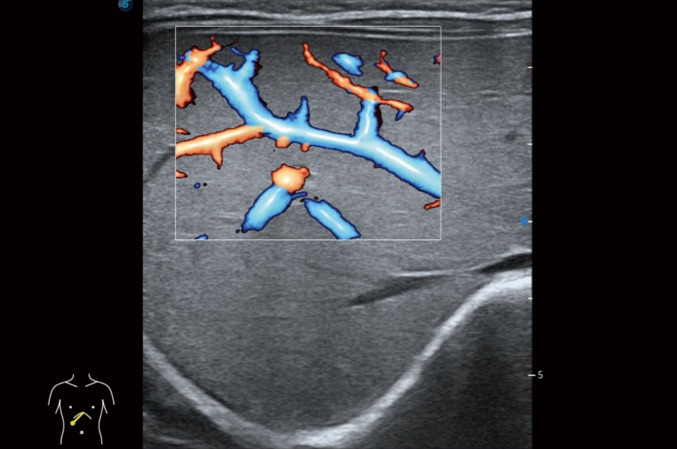

高分辨率血流成像技術(shù)提高了對(duì)低速血流信號(hào)的檢測(cè)能力。在提高空間分辨率的同時(shí),也克服了血流外溢現(xiàn)象,為用戶(hù)提供更加真實(shí)的血流動(dòng)力學(xué)信息。